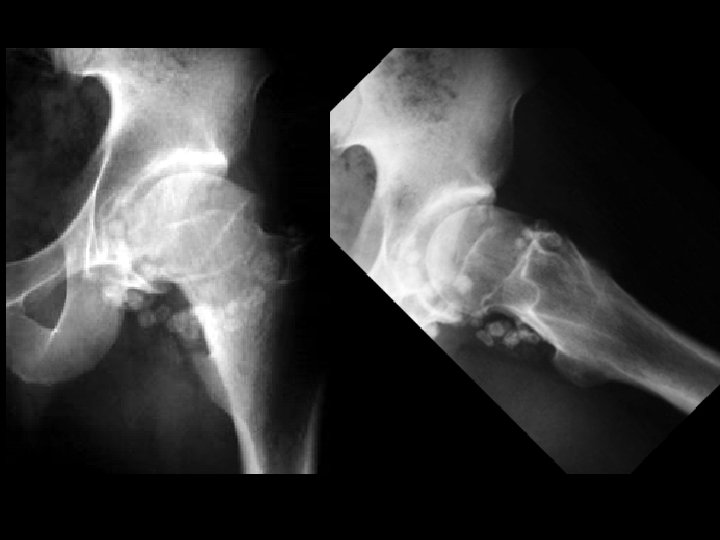

Synovial osteochondromatosis • Findings: – Multiple round calcified masses in the joint space – Erosions on both sides of the joint – Single joint involvement • ddx: – Primary (idiopathic) – Secondary to OA